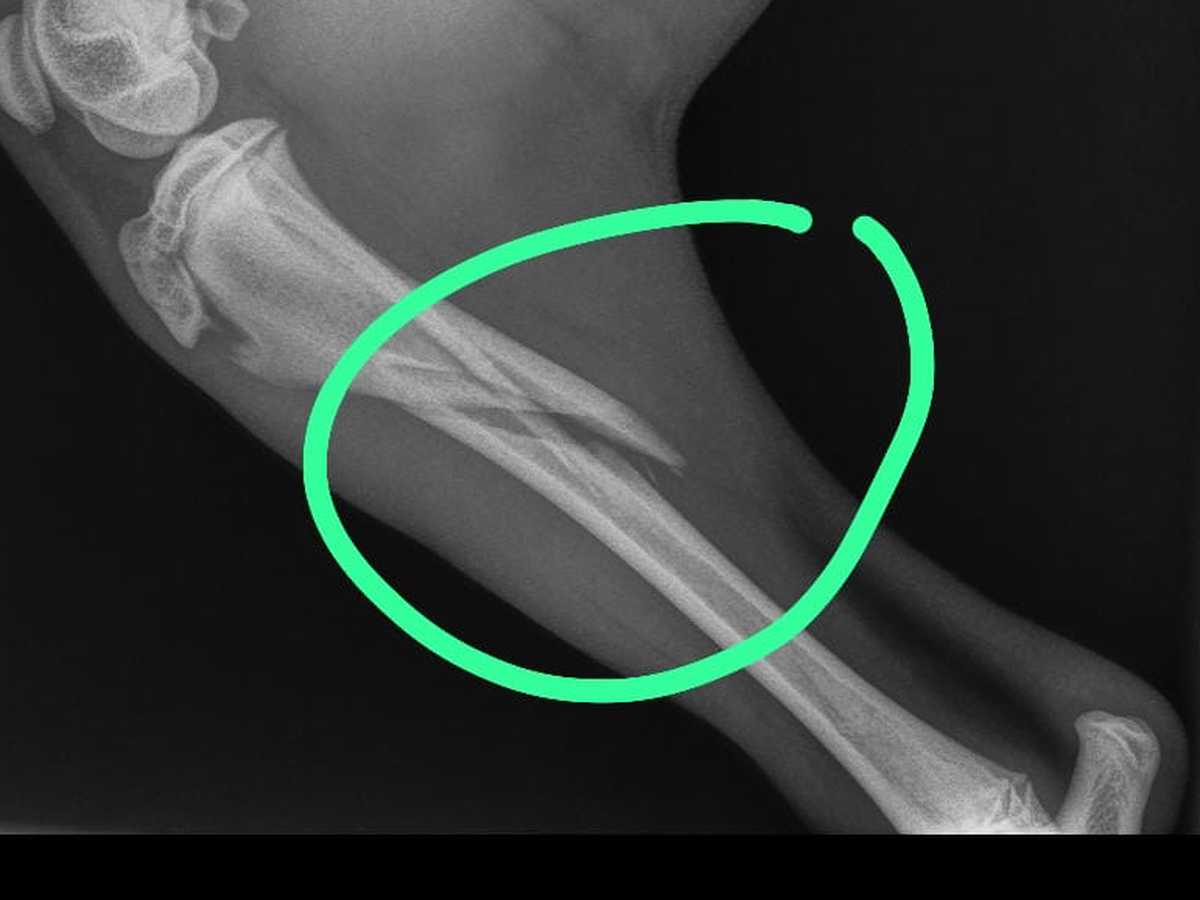

Mijn naam is percy zit in groot probleem mijn lieve hond puppy Bintang heeft ze pootje gebroken en is hoge kosten gekomen hoop dat ik hier mensen zijn die me kunnen helpen